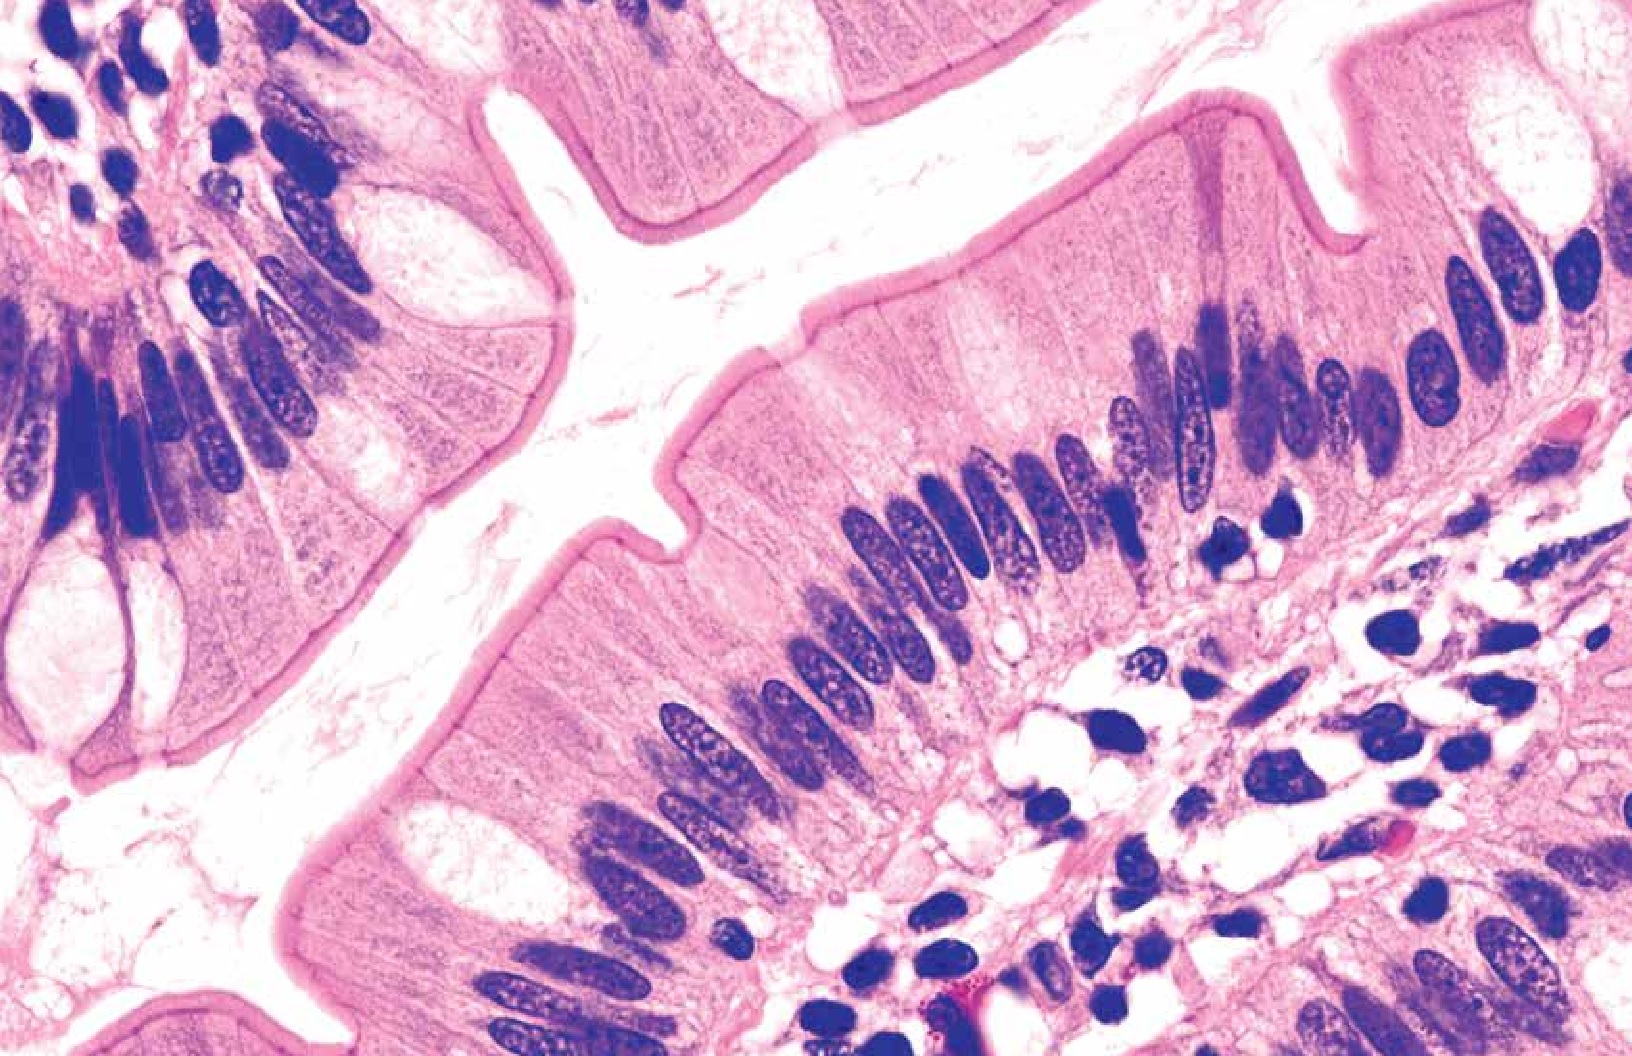

Hematoxilina de Cole

La Hematoxilina de COLE de la línea de Histo-Line, es una formulación de hematoxilina utilizada en histopatología para la tinción de células nucleares. Puede utilizarse en lugar de la Hematoxilina M (Hematoxilina de Mayer). A diferencia de la Hematoxilina M (utilizada sólo en el método de tinción progresiva), la Hematoxilina de COL se utiliza en los métodos de tinción progresiva y regresiva.

El complejo hemateína-mordante cargado positivamente se une entonces con los iones fosfato cargados negativamente del núcleo del ADN, creando la coloración azul característica. La Hematoxilina de COL modificada de Histo-Line se oxida con yodo y está lista para su uso inmediato.